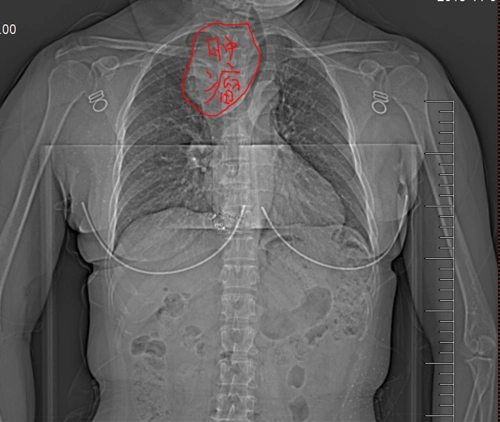

胸椎术后后凸角较术前减小11

谈谈胸骨后甲状腺肿手术治疗的要点

巨大胸骨后甲状腺肿瘤经过颈部成功切除